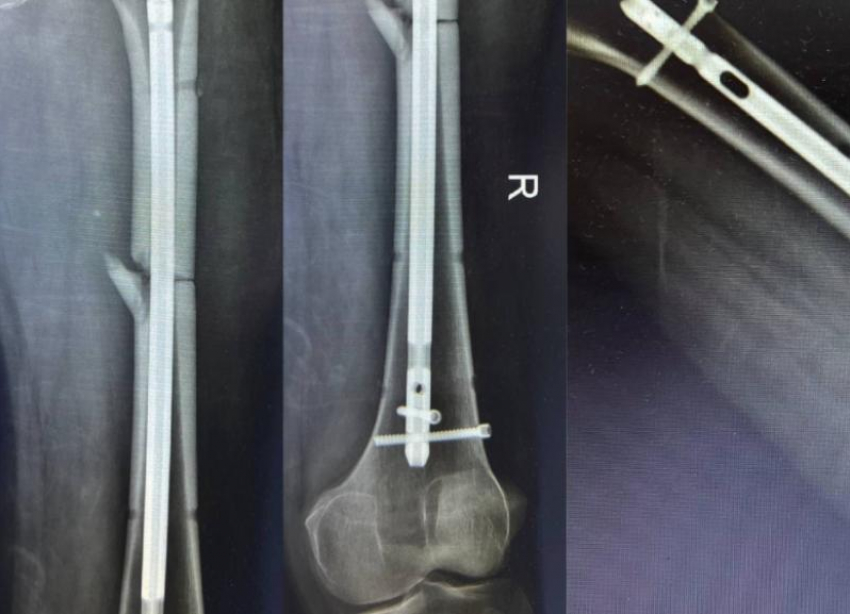

Пострадавший с открытым оскольчатым переломом правой бедренной кости и смещением отломков был доставлен в медучреждение. Такие травмы относятся к разряду крайне тяжелых и требуют незамедлительного хирургического вмешательства.

Для лечения выбрали интрамедуллярный блокируемый остеосинтез, позволяющий добиться прочной фиксации костных отломков с помощью специального штифта и создать условия для ранней реабилитации.